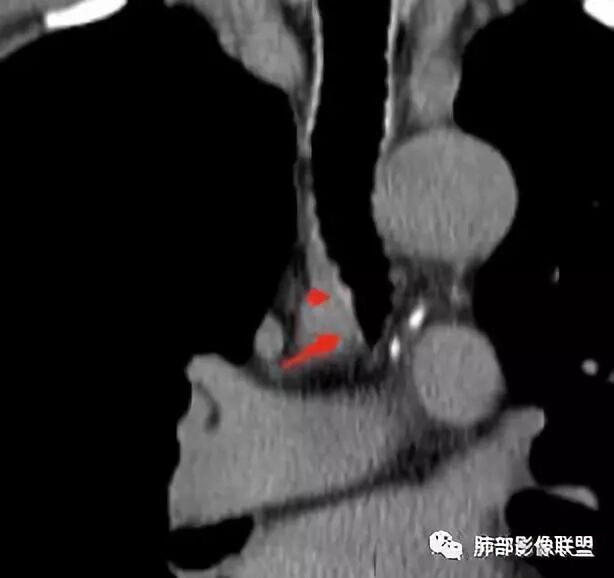

南边分析:针对本例,病灶跨气管壁内外生长,常规跨内外的有:恶性肿瘤为主,其次就是神经源性、平滑肌瘤;常规的思维:跨内外就要看结构的变化气管的优势在于软骨相对密度高,而且成C型

我们如何分析这个病例?冠状位:软骨密度稍高;病灶区软骨部分区域不连续,外围连续,提示病灶推移为主,不是破坏为主;如果破坏,应该这些软骨显示不清,移位不明显

病灶从软骨见推移开,跨内外,因此定在良性。恶性是侵犯,破坏为主,如果破坏,应该这些软骨显示不清,移位不明显,不是推移为主这例病变定在良性,我们就要考虑:1、软骨之间的平滑肌来源;2、神经源性

病例小结      气管神经鞘瘤属于罕见的气管良性肿瘤,一般气管良性肿瘤或腔内或腔外生长的结节样改变,恶性肿瘤呈腔内外生长,但本例肿块向腔外生长,呈“冰山样改变”,即肿瘤的腔内部分较小而腔外部分较大,无周围组织侵犯。因此肿瘤腔内外生成不能作为鉴别气管良恶性肿块的绝对依据。        因此冠(矢)状位多平面观察、软骨是否破坏、气管壁有无增厚等细节观察,对于鉴别气管肿块良恶性有重要的参考性。

1.气管隆凸上右前壁不规则结节影,部分突入腔内,南边老师观察有推挤软骨环“破土而出”的形态特征。注意没有沿气管粘膜表面生长蔓延的生物学行为。

2.影像学病灶占据腔内外,但病灶边缘十分清楚。这点倾向良性。